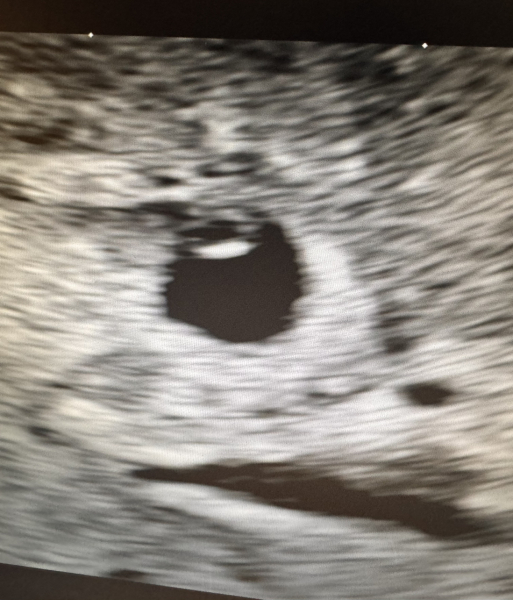

@Sunandsea13 this was my 6week scan & we could see the heartbeat fluttering away but they say the heartbeat is only visible from 6 weeks. I think all they would be able to tell you at 5+4 is that it’s in the right place if that’s what you’re worried about?

@Sunandsea13 This was my scan at estimated 5 weeks, gestation sac, yolk sac and fetal pole seen, about 2mm, and no heartbeat at this stage.